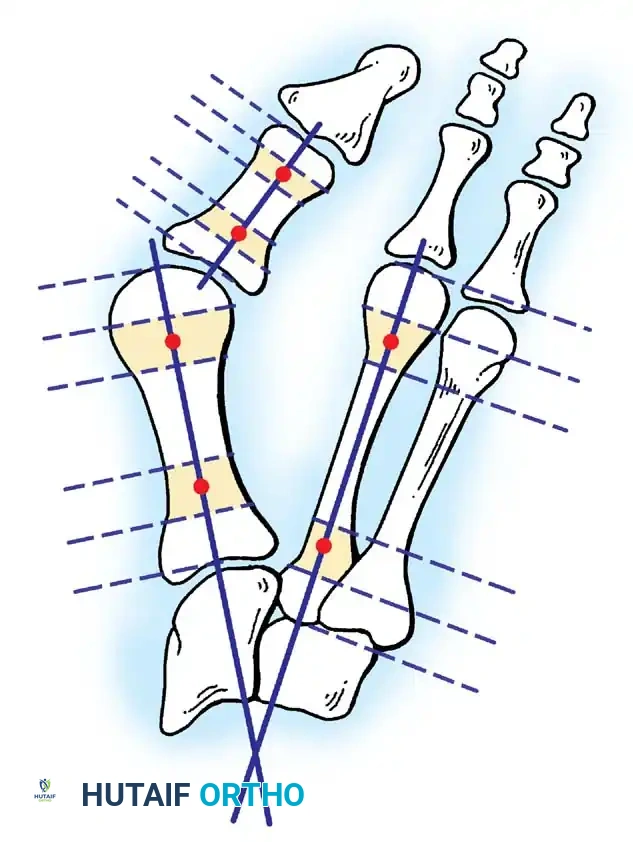

Hallux valgus (lateral deviation of the great toe) is not a single disorder, as the name implies, but a complex deformity of the fi rst ray that frequently is accompanied by deformity and symptoms in the lesser toes (Fig. 78-1). Often the angle between the fi rst and second metatarsals is more than the 8 to 9 degrees usually considered to be the upper limits of normal. The valgus angle of the fi rst metatarsophalangeal joint also is more than the 15 to 20 degrees considered to be the upper limits of normal (Fig. 78-2). If the valgus angle of the fi rst metatarsophalangeal joint exceeds 30 to 35 degrees, pronation of the great toe usually results. With this abnormal rotation, the abductor hallucis, which is normally plantar to the fl exion-extension axis of the fi rst metatarsophalangeal joint, moves further plantarward (Fig. 78-3). In this case, the only restraining medial structure is the medial capsular ligament with its capsulosesamoid portion (inserting into the base of the proximal phalanx) (Fig. 78-4) and capsulophalangeal portion (inserting into the plantar plate). The adductor hallucis, which is unopposed by the abductor hallucis, pulls the great toe further into valgus, stretching the medial capsular ligament (particularly the capsulosesamoid), attenuating this structure, and allowing the metatarsal head to drift medially from the sesamoids. In addition, the fl exor hallucis brevis, fl exor hallucis longus, adductor hallucis, and extensor hallucis longus increase the valgus moment at the metatarsophalangeal joint, further deforming the fi rst ray. The deep transverse intermetatarsal ligament runs between the plantar plates at the metatarsophalangeal joints and does not insert into bone on the adjacent sides of the metatarsal heads. Finally, the sesamoid ridge on the plantar surface of the fi rst metatarsal head (the crista) fl attens because of pressure (abutment) from the tibial sesamoid (Fig. 78-5). With this restraint lost, the fi bular sesamoid displaces partially or completely into the fi rst intermetatarsal space (see Fig. 78-2). In this situation, the patient is bearing less weight on the fi rst ray and more on the lesser metatarsal heads, increasing the likelihood of transfer metatarsalgia, callosities, and stress fracture of a lesser metatarsal.

Two other anatomical variants involving the articular surface of the fi rst metatarsophalangeal joint can lead to hallux valgus. In the fi rst variant, the articular surface of the metatarsal head is offset, resembling a scoop of ice cream sitting at an angle on a cone (Fig. 78-6). This has been described as the distal metatarsal articular angle (see Fig. 78-8). In the second, the articular angle of the base of the proximal phalanx in relation to its longitudinal axis is offset. This has been described as the phalangeal articular angle. Although the normal range of these angles is generally considered to be 7 to 10 degrees for the phalangeal articular angle and 10 to 15 degrees for the distal metatarsal articular angle, exact measurements are diffi cult to reproduce because of the variability of radiographic and measurement techniques. Increasing evidence indicates, however, that the failure to correct these two deformities, especially the distal metatarsal articular angle, can cause unsatisfactory results after surgery in some patients. Forceful straightening of the hallux should be avoided if it sacrifi ces tarsalgia. The entire forefoot must be evaluated for these multiple components of hallux valgus before surgical planning is complete and recommendations can be made to the patient. The controversy continues over which deformity is the essential lesion in hallux valgus: metatarsus primus varus or lateral deviation of the great toe. Each is incriminated as the cause of the other. The strongest data probably support lateral deviation of the great toe as the primary deformity in most patients, followed by medial angulation of the fi rst metatarsal, but metatarsus primus varus may be the principal cause in adolescents. Further controversy surrounds the role of footwear as the prime offender in the development of hallux valgus. Most orthopaedic surgeons have seen unilateral hallux valgus when both feet are clinically and radiographically the same structurally except that one foot has a bunion deformity and the other foot is normal. Evidence supports that hallux valgus may be familial, especially when it occurs in adolescents. Although no study of shod and unshod societies has implicated inappropriate footwear as the sole cause of hallux valgus, after genetic factors, binding, unphysiologically designed footwear probably is the major cause in modern societies. Hypermobility of the fi rst ray also has been suggested as a causative factor in the development of hallux valgus and fi rst metatarsal varus, but this is controversial. Coughlin and Shurnas, Myerson and Badekas, King and Toolan, and Faber et al. offer excellent discussions of this problematic area. Finally, certain anatomical and structural abnormalities almost certainly play a causative role in hallux valgus. Pronated fl atfeet, abnormal insertion of the posterior tibial tendon, increased obliquity of the fi rst metatarsomedialcuneiform joint, an abnormally long fi rst ray, incongruous articular surfaces of the fi rst metatarsophalangeal joint, and excessive valgus tilt of the articular surface of the fi rst metatarsal head and proximal phalangeal articular surface may contribute singly or in combination to the deformity and infl uence the recommended treatment. Hypertrophy of the medial eminence has been described as a component of hallux valgus deformity since the earliest reports; however, more recent investigations, including those of Thordarson and Krewer, have found that bony proliferation is not a component of the pathoanatomy of hallux valgus and that the prominence of the medial eminence results from the combination of metatarsus primus varus and medial deviation that uncovers the articular surface. Thordarson and Krewer compared radiographs of 50 feet in patients who had surgery for hallux valgus deformity with radiographs of 50 feet from a control group without hallux valgus deformity and found little difference in the average width of the medial eminence (4.4 mm and 4.1 mm). With more than 130 operations recommended for the treatment of hallux valgus, it is practical to describe only

Inadequate vascularity or sensibility should be investigated thoroughly before bunion surgery is considered. In addition, the position of the articular surface of the metatarsal head in relation to the longitudinal axis of the fi rst metatarsal should be determined (Fig. 78-8). Standard preoperative radiographs should include standing dorsoplantar and lateral views, a nonstanding lateral oblique view, and axial sesamoid views (Fig. 78-9). The hallux valgus angle and the fi rst-second intermetatarsal angle should fi rst be drawn on the standing dorsoplantar view by bisecting the shafts of the bones (Fig. 78-10), with an awareness of the normal ranges. These angles are most frequently cited as guidelines for treatment decisions, but Donnelly et al. reported that interobserver measurements of the hallux valgus angle varied by approximately 6 degrees and of the intermetatarsal angle by 4 degrees. They cautioned that potential errors in measurement should be considered when these parameters are used to make treatment decisions. The hallux valgus interphalangeus angle and any evidence of degenerative arthritic changes at the fi rst metatarsophalangeal or metatarsocuneiform joints should be documented. Oddities may be present and, if overlooked, may compromise a technically well-done procedure. Mann emphasized that the presence of an os inter-

Fig. 78-8 A, Determination of position of articular surface of metatarsal head in relation to longitudinal axis of fi rst metatarsal. B, Measurement of distal metatarsal articular angle at time of surgery. Markings are at medial and lateral margins of articular surface of fi rst metatarsal head and longitudinal axis of fi rst metatarsal shaft. metatarseum between the bases of the fi rst and second metatarsals might preclude the effectiveness of a soft-tissue procedure alone to provide suffi cient correction of the increased intermetatarsal angle. Likewise, accessory sesamoids and prominent ungual tuberosities at the interphalangeal joint contribute to a painful callus at the tibial side of this joint. An os tibialis externum frequently is associated with excessive hallux valgus interphalangeus. Varus of the fi rst metatarsal might be a signifi cant part of the overall deformity of the foot even with an intermetatarsal angle of less than 10 degrees. Metatarsus varus with a relatively small hallux valgus angle (15 to 20 degrees) may produce signifi cant deformity even though the angles are not excessive. The usefulness of computer-assisted compared with manual measurement of the intermetatarsal angle, hallux valgus angle, and distal metatarsal articular angle is still uncertain. Both methods have closer interobserver and intraobserver correlation in measurement of the intermetatarsal angle and hallux valgus angle than in measurement of the distal metatarsal articular angle. The reliability of either method has such a wide range (5 degrees), however, that measurements of these angles, although useful as a guide, do not provide a completely reliable indication of the magnitude of deformity. Condon et al. suggested that the reliability of the intermetatarsal angle can be improved by careful technique and by making the measurements at least twice and averaging them. Schneider et al. reported two methods of determining angular measurements based on distinctly different reference points: (1) a longitudinal axis of the fi rst metatarsal using middiaphyseal reference points, and (2) a center-head technique using a center head (center of the articular surface) and center base

(center of the proximal diaphysis) as reference points. They found that measured correction of the hallux valgus and intermetatarsal angles varied by approximately 9 degrees depending on which reference points were used. Recommendations of Coughlin, Saltzman, and Nunley (American Orthopaedic Foot and Ankle Society Ad Hoc Committee on Angular Measurements) included standardized radiographic technique, specifi c placement of reference points (Fig. 78-11), use of a protractor rather than a goniometer for measurements, and, after distal osteotomies, dual measurements using a center-head technique and a Mose sphere.